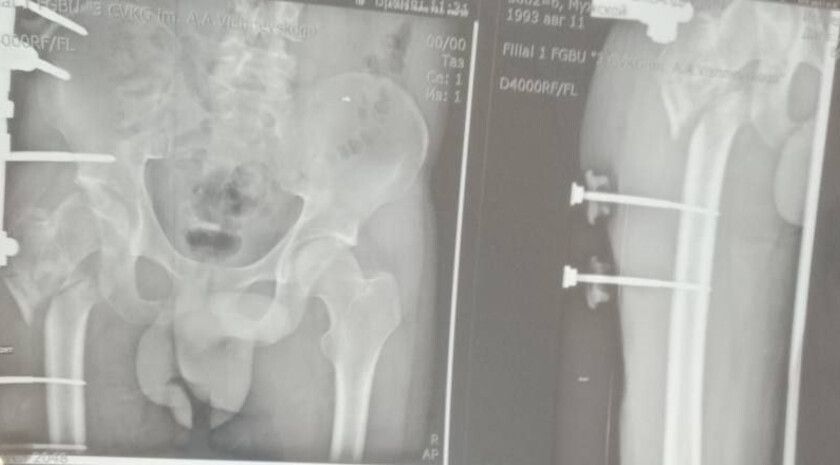

Об этом сообщила министр здравоохранения ЛНР Наталия Пащенко.Руководитель Минздрава рассказала, что борьба сержанта из ЛНР, мужчины 1993 года рождения, длилась три с половиной года. За это время он проходил лечение в десяти госпиталях, в том числе в...

Уникальная операция в Луганской республиканской клинической больнице вернула ветерану специальной военной операции (СВО) возможность ходить без хромоты. Об этом сообщила министр здравоохранения ЛНР Наталия Пащенко. Руководитель Минздрава...

Об этом сообщила министр здравоохранения ЛНР Наталия Пащенко в своем телеграм-канале.Боец ушел на фронт 25 февраля 2022 года, прошел через горнило Херсонщины, а тяжелое ранение получил 28 августа.«Из-за обширных повреждений и многократных операций...

Об этом сообщила министр здравоохранения ЛНР Наталия Пащенко.Боец ушел на фронт 25 февраля 2022 года, прошел через горнило Херсонщины, а тяжелое ранение получил 28 августа.«Три с половиной года борьбы. Десять госпиталей. И одна операция, которая...

Уникальная операция в Луганской РКБ вернула ветерану СВО возможность ходить без хромотыТри с половиной года борьбы. Десять госпиталей. И одна операция, которая изменила всё.История сержанта из ЛНР, 1993 года рождения — это не просто медицинский отчёт....